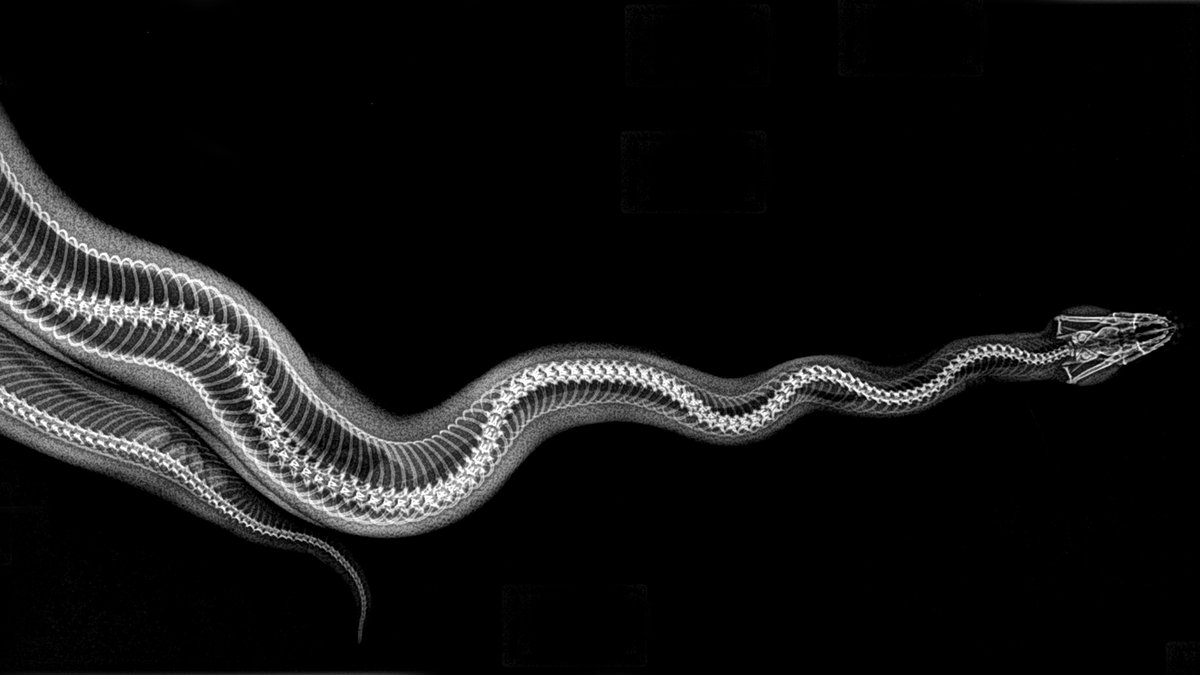

Serpiente boa pitón